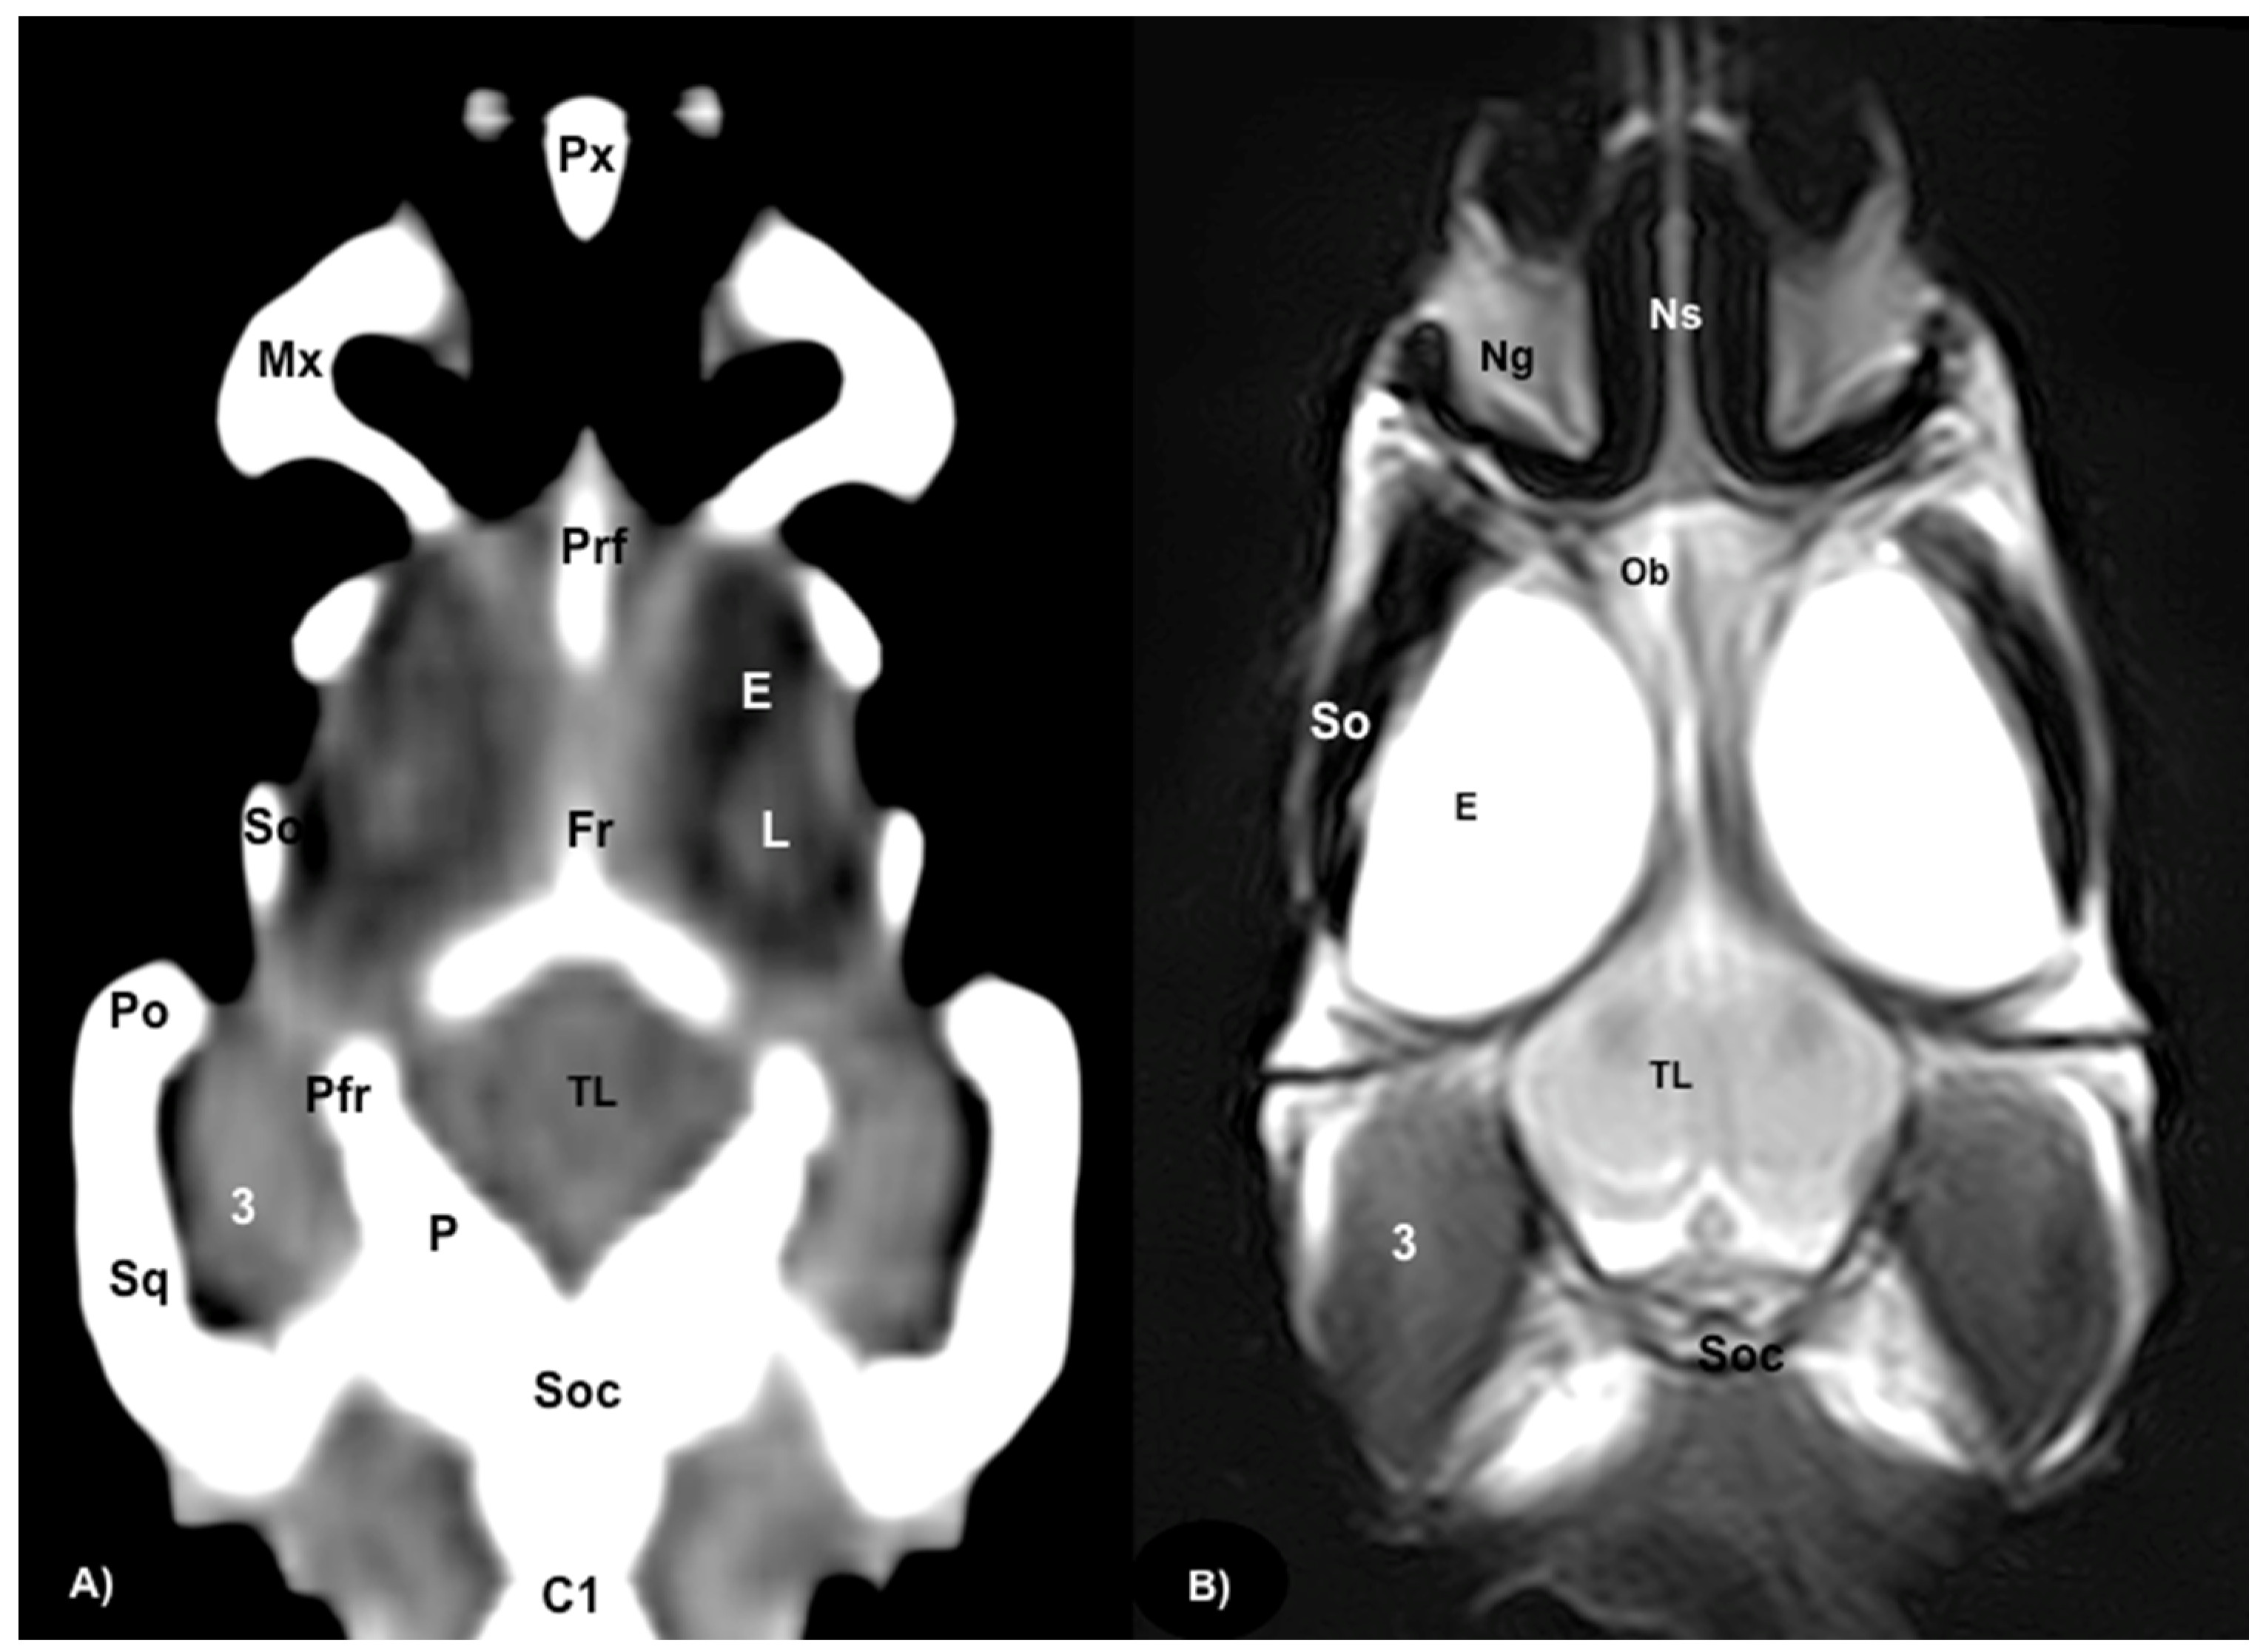

3.1. Anatomical Sections

3.2. Computed Tomography (CT)

3.3. Magnetic Resonance Imaging (MRI)